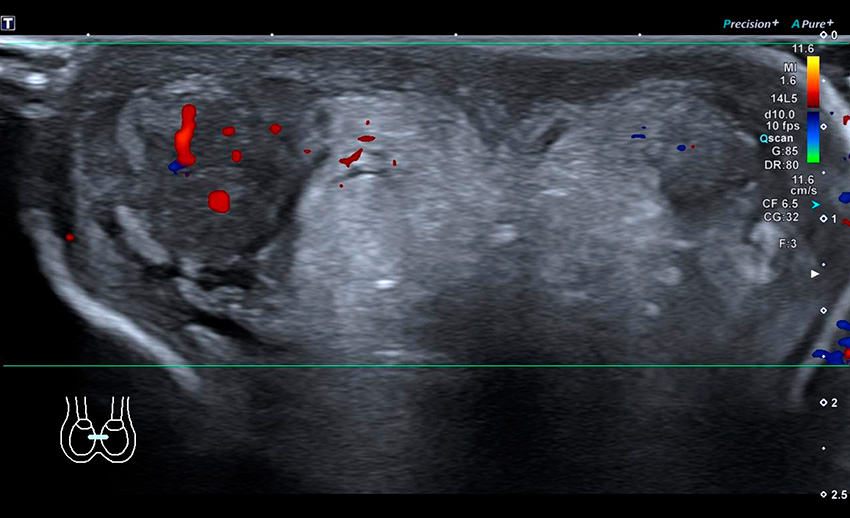

Idiopatiskt skrotalödem. Uttalat ödem och förtjockning ses i skrotalväggen men testikeln har normalt utseende. Tillståndet är oftast kliniskt tydligt men har också en mycket typisk bild på ultraljud, om tveksamhet skulle föreligga.